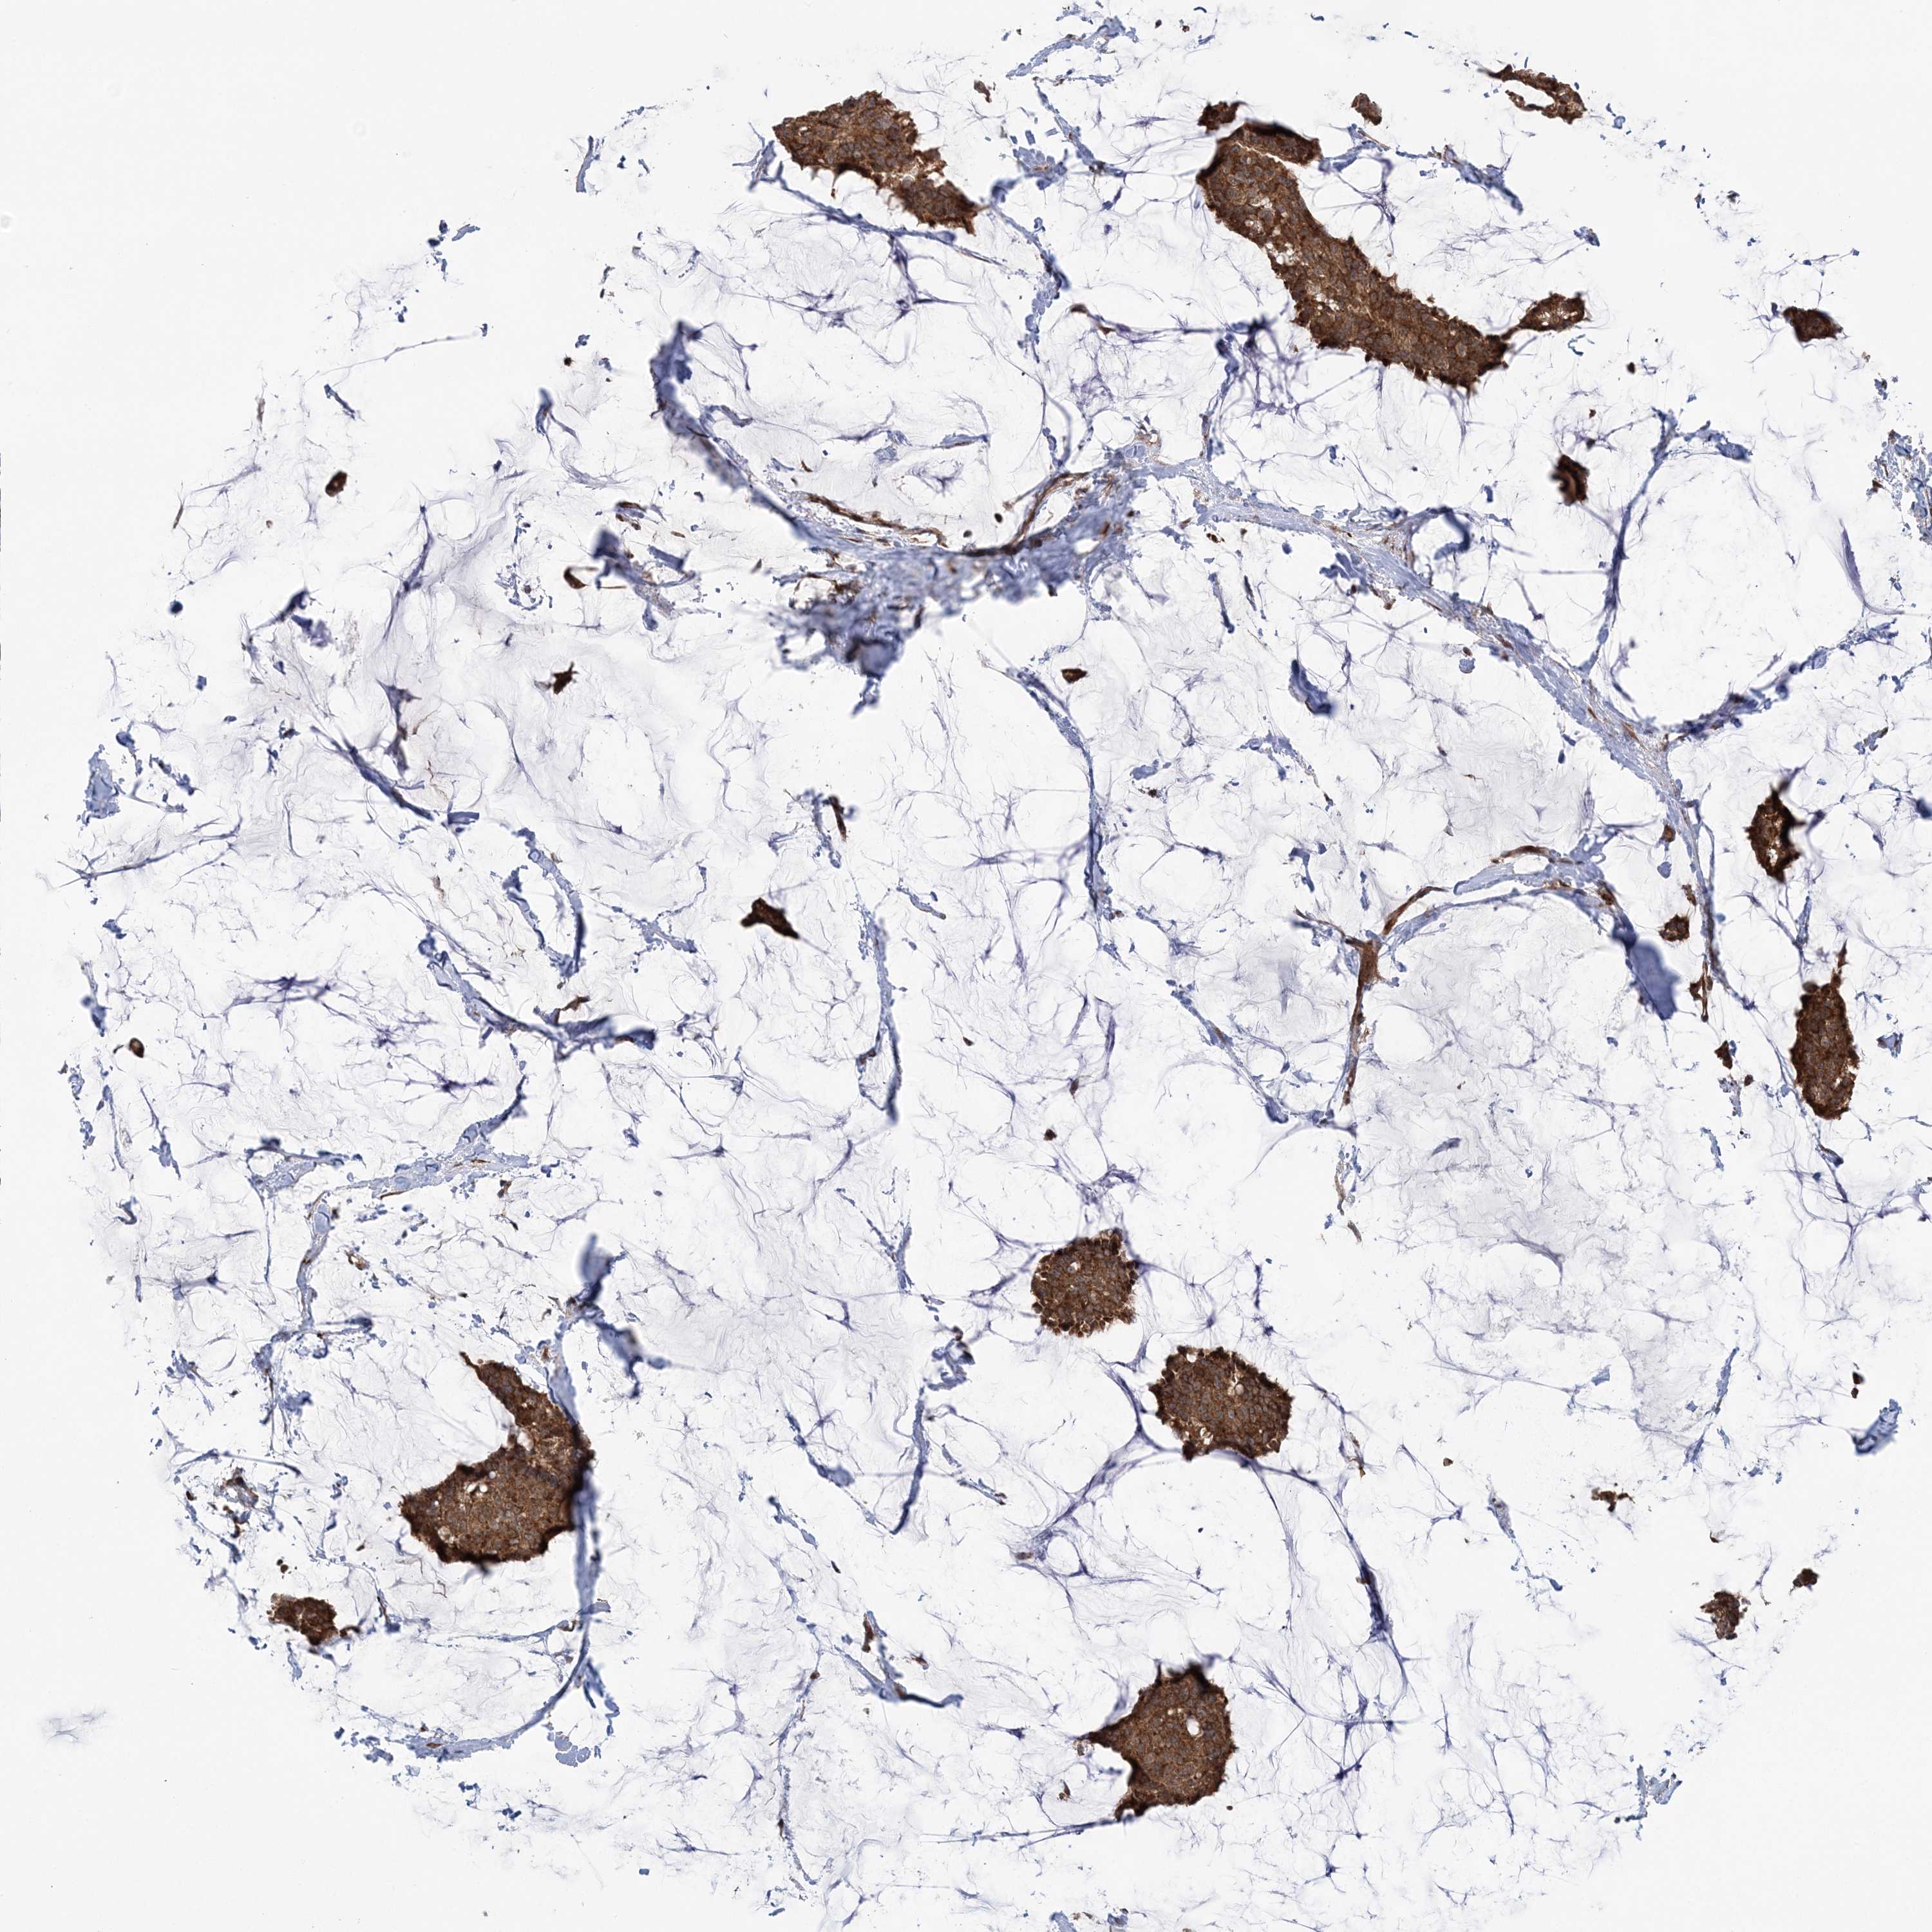

BRCA TCGA BRCA VALIDATION PROTEIN EXPRESSION

Breast cancer

Human cancer